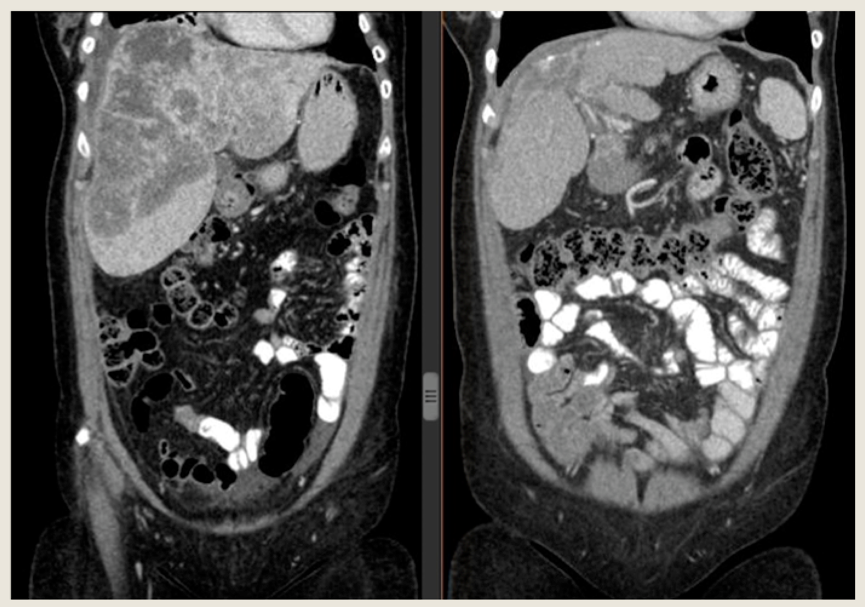

最后Lim教授分享了1例临床病例,这是1例66岁中国女性乳腺癌患者,初诊为局部晚期乳腺癌cT2N1,浸润性导管癌,3级,ER/PR/HER2均为阴性。接受AC化疗4周期,序贯紫杉醇卡铂周疗12个周期。新辅助化疗后手术,取得病理完全缓解(pCR)。然而,术后9个月,患者出现肝脏和淋巴结转移。患者拒绝静脉化疗和参加临床试验,期望接受不会引起脱发的化疗方案。给予患者口服长春瑞滨 30mg,每周3次联合环磷酰胺,50mg。4个月后疗效评估为PR。

图. 治疗前后的肝脏病灶变化,疗效评价为PR